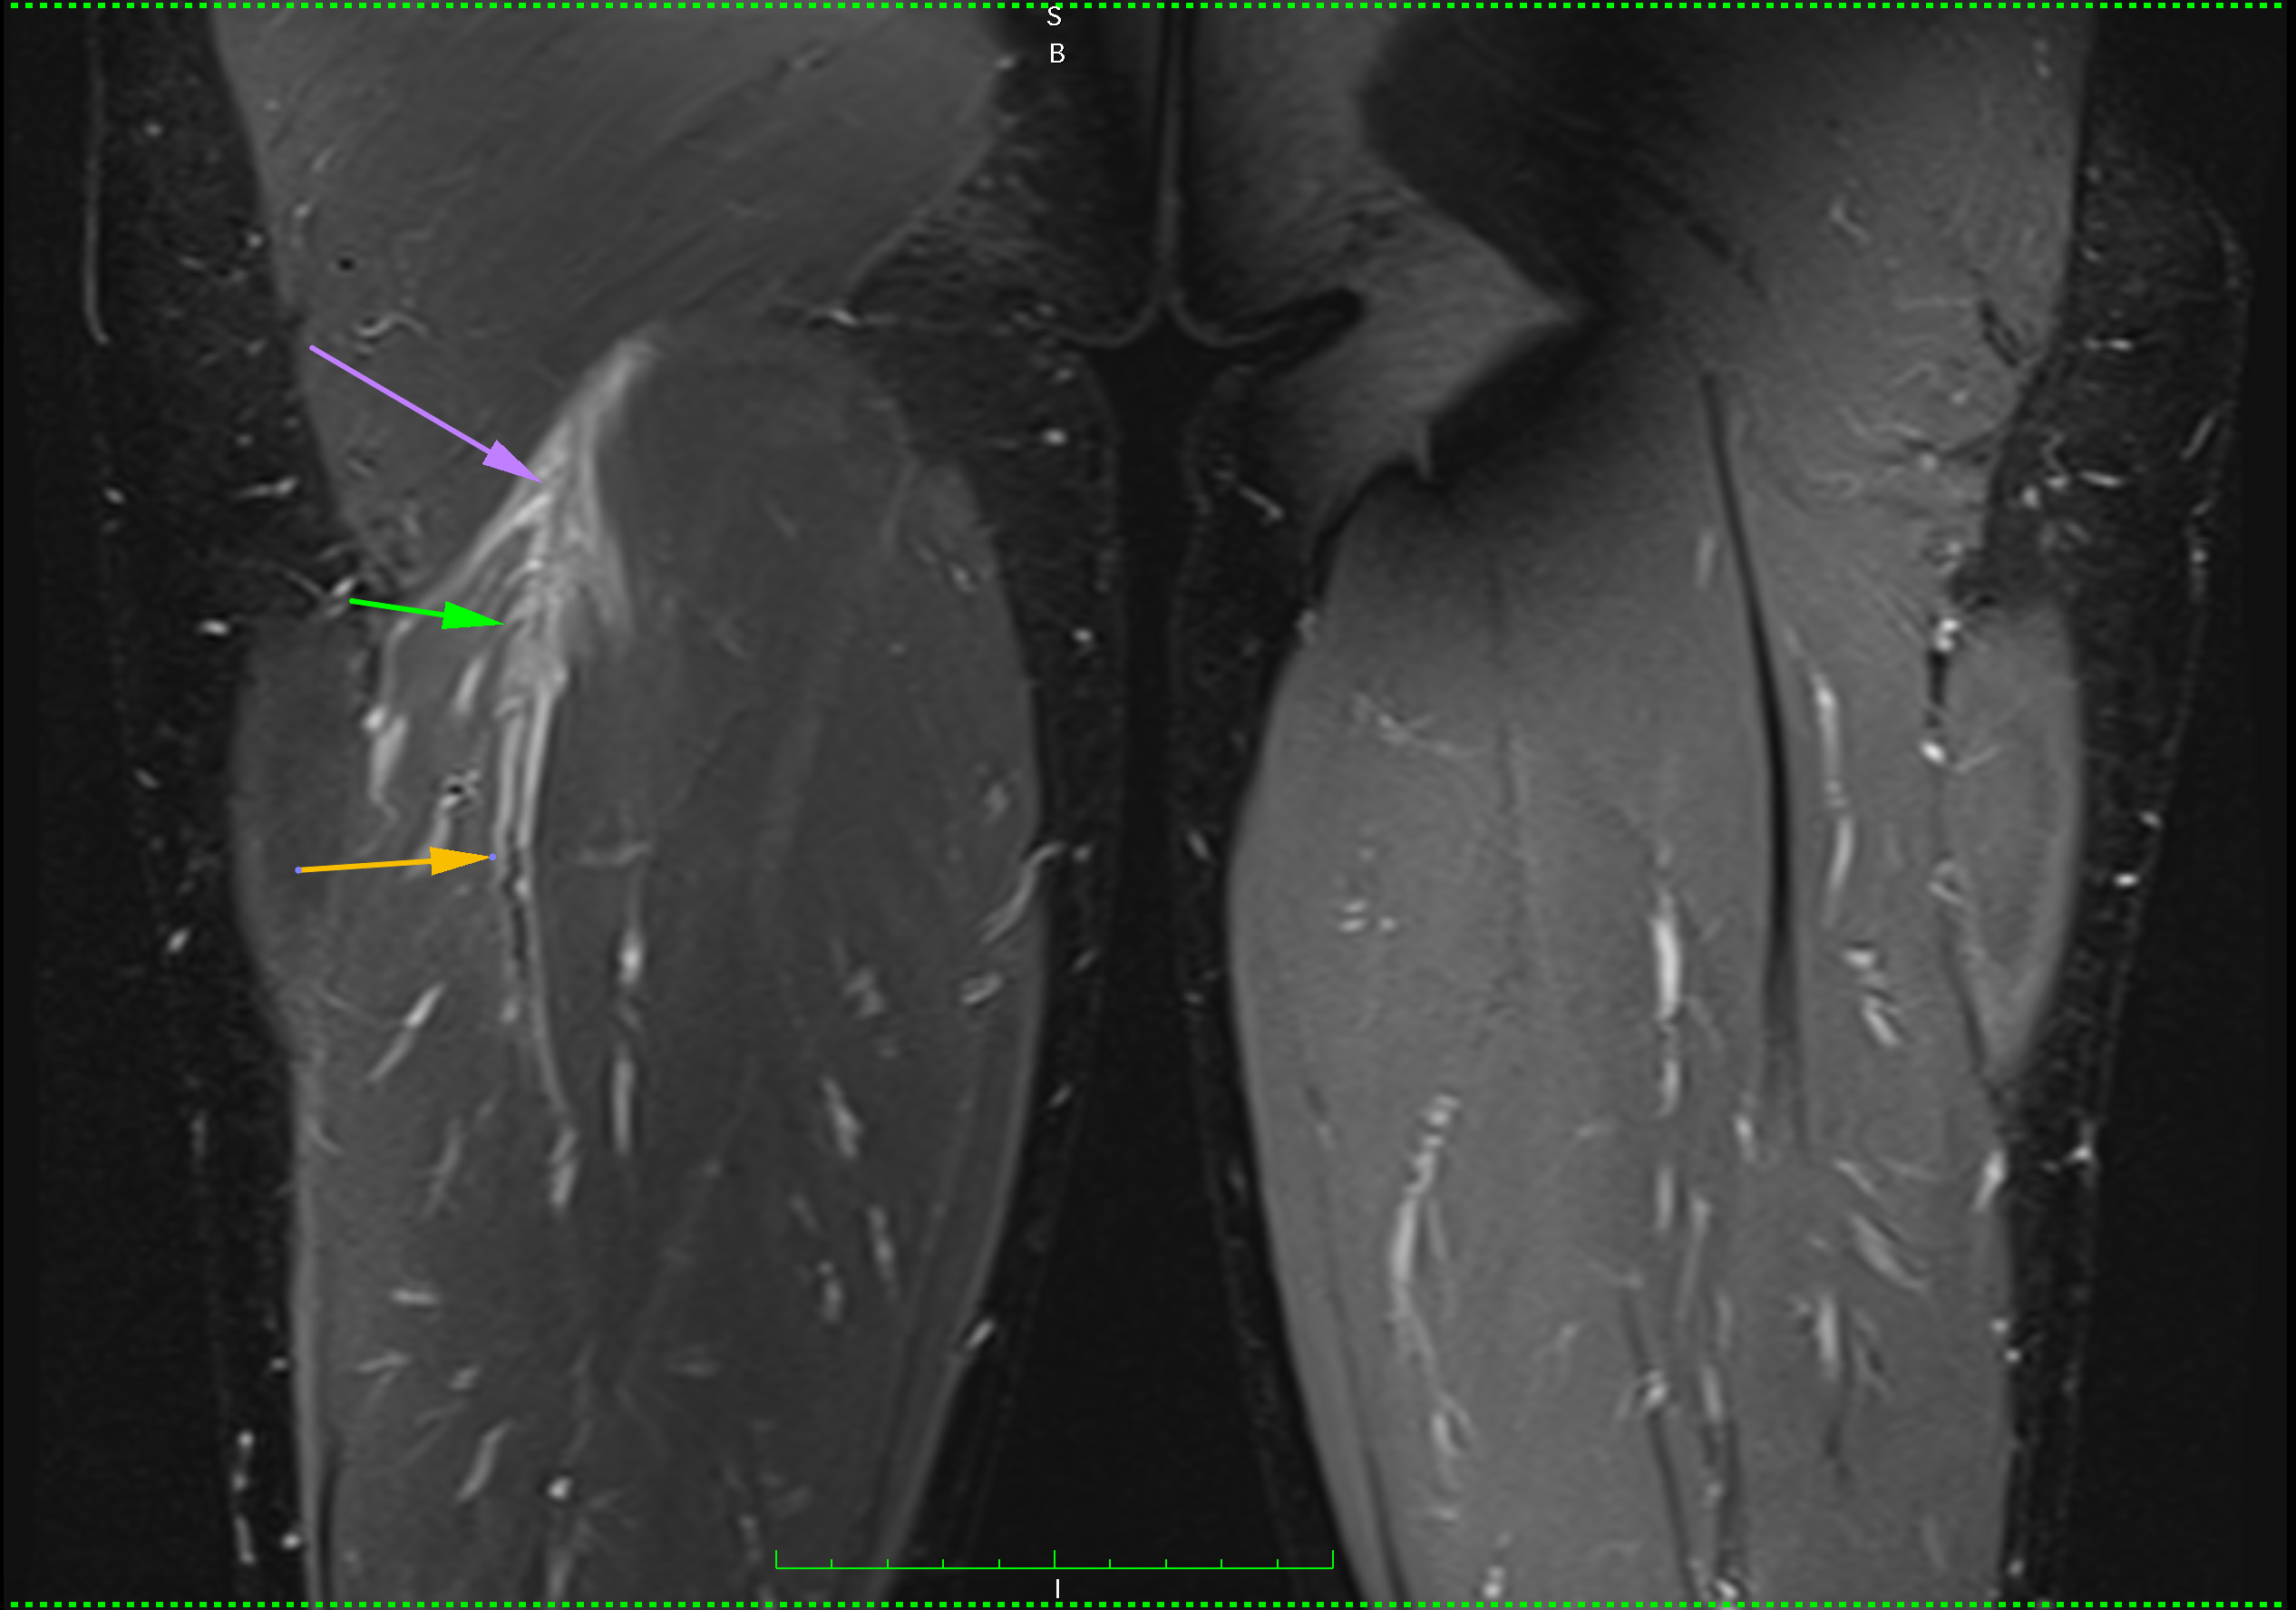

A few days ago, a new case-injury arose. A long-time patient and a dear friend injured himself during a soccer match by trying to play a heel pass. Immediately it was seen that the injury is severe. MRI confirmed expectations, intramuscular hamstring biceps tendon tore. It is a very complicated and long healing injury and usually misdiagnosed as a simple muscle rupture.

MRI of hamstring intramuscular biceps tendon injury